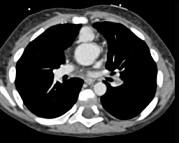

问题 患者,男性,8岁,发绀、气促,易感冒,彩超提示只见一个心室,CT检查如图所示,请选择正确的选项 ( )

选项 A、考虑三尖瓣狭窄 B、右前斜位示左心房增大,心后上缘后突压迫冲钡食管 C、左前斜位示心影向后下方突出 D、考虑二尖瓣狭窄

答案 BCD